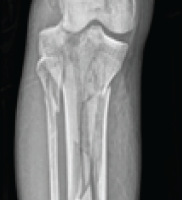

Eighty patients were taken in this study who had Humerus mid-shaft fractures. They were divided into two groups. In ABP group, only 1 case showed superficial infection, whereas in ORIF group,2 cases showed infective non-union. 2 cases of group-1 and 5 cases of group-2 had postoperative radial nerve palsy which all of them recovered spontaneously. Hence, the rate of palsy is more with ORIF group which is significant [p-value<0.5]. One case of ABP resulted in non-union whereas two cases of ORIF showed nonunion due to infection, out of which one case went through grafting and the other case was lost in follow-up (Table 1).We studied that the range of motion at shoulder joint is more with ABP group comparatively as the p-values are significant more with flexion, extension, abduction, internal rotation and external rotation. Out of 40 cases of ABP, 19 cases showed score34, 10 cases showed 33,10 cases-32,1case showed 30.Outof 40 case s ORIF, 10 cases showed 34, 7-33, 9-32, 2-28, 1-24, 1-22. Because of less soft tissue dissection, ABP shows good shoulder outcome (p-value<0.05) (Table-2).In ABP group, 24cases showed 100,1-98,1-975.InORIFgroup,21cases showed100,15-95,3-90,1-85. Hence, ABP shows better elbow outcome than ORIF cases (Table-3).ABP cases shows early radiological union comparatively{12weeks-mean} with p-value<0.05 (Table-4).The surgical time is more with ABP since it is a closed reduction method (Table-5). The mean number of c-arm shoots was 104.28 in Group-1 and 8.05 in group-2. There was no difference in the outcome when compared to age, sex, side or obesity.

Thakor et al. highlighted the construct’s ability to withstand biomechanical stresses through relative stability[12]. Hence in our analysis, ABP cases had radiological union by 12.75 weeks (mean)and ORIF cases had by 14.75 weeks (mean). Even though there is absolute stability in conventional method, ABP showed less time period of time. Yang’s comparison of MIPO and ORIF favoured ABP for its superior safety and functional outcomes [13], and Bhandra et al. confirmed its safety in straightforward fracture patterns when performed by experienced surgeons [14]. In our study, mean UCLA shoulder score was 33.15 in ABP and 31.53 in ORIF. The mean Mayo elbow score was 98.13 in ABP and 97 in ORIF. Therefore, the functional outcome is better in ABP group similarly to the previous studies. Anatomical safety remains paramount. Apivatthakakul et al. identified high-risk zones for nerve injury during screw placement, emphasizing the need for precise technique [15]. Suwannaphisit et al. further demonstrated the variability in radial nerve anatomy, underlining the importance of preoperative planning and intraoperative vigilance [16]. 5 cases of ORIF and 2 cases of ABP showed postop radial nerve palsy in our research. All of them recovered spontaneously. The reason to have radial nerve palsy in ABP is because not having knowledge about the precise location of radial nerve and it varies in each individual and may have anatomical anomalies, and uncontrolled drilling where the drill bit can hit the nerve posteriorly. ABP preserves periosteal blood supply, limits soft tissue disruption, and allows micromotion conducive to callus formation—all factors that support fracture healing and reduce complications such as infection and non-union. Although technically demanding, ABP with DCP represents a promising and practical alternative to traditional plating methods, especially when performed by skilled surgeons. This study is a reliable research as it covers a good sample in both groups with no sexual bias and the most common age group and followed the cases for the period of 1year. However, it doesn’t include the elderly population where DCP cannot be used, doesn’t include post-traumatic radial nerve palsy (GA-3C with wrist drop), as whether ABP does not involve radial nerve exploration or the need of exploration is a must, as most of them are conserved in all types of nerve injury except in transection. These are its limitations and a meta-analysis should be done, which can include all types of open fractures with and without radial nerve palsy or should be studied alone.